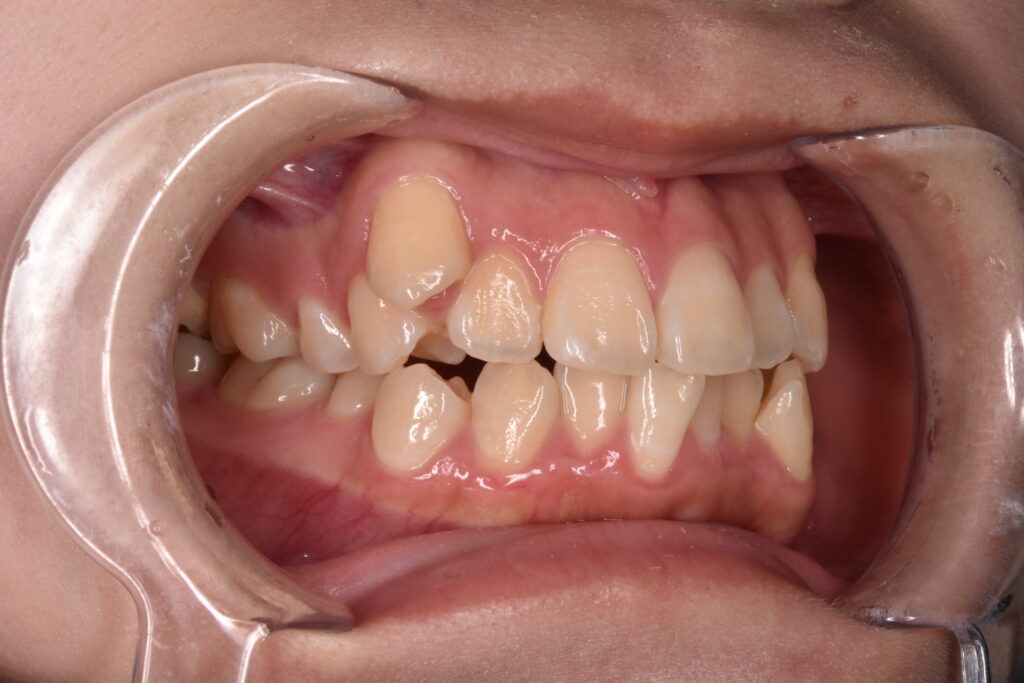

10代女性 以前より八重歯をなくしたいと悩んでいて、高校卒業と同時に矯正を始めたいと、ご家族でご相談にご来院くださいました。

Before

1番気になっていた右の八重歯のはの動きが見れます